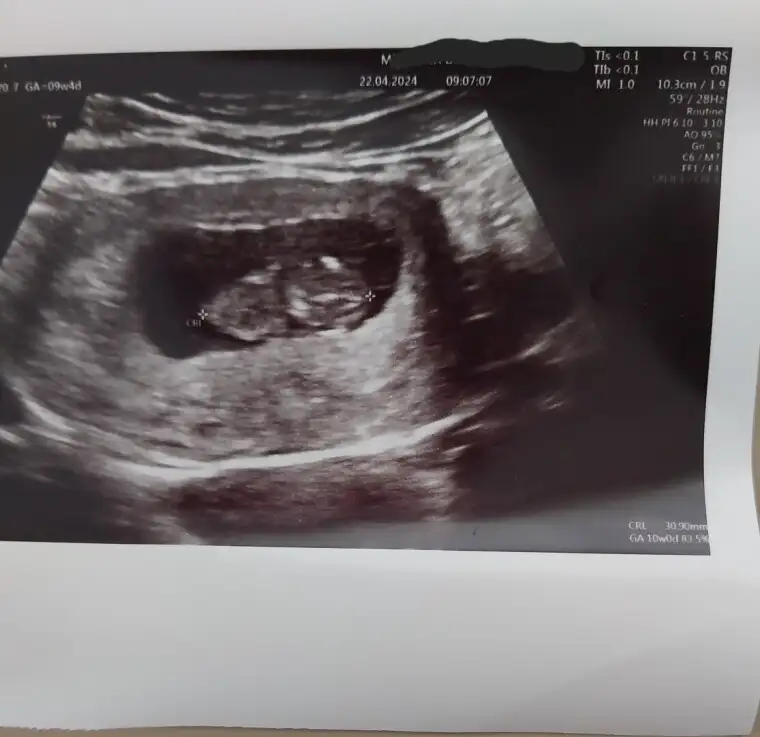

Benimkine de bakar mısınız 😊 10+2

• IMG_20240422_124357.webp

IMG_20240422_124357.webp

8,3 KB · Görüntüleme: 72